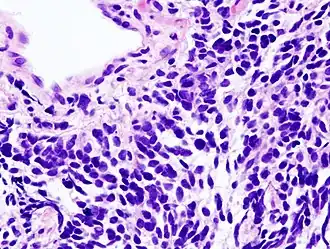

Carcinoma de células pequeñas.

Carcinoma de células pequeñas (SCLC)

_by_core_needle_biopsy.jpg)

Cerca de un 15 % de todos los carcinomas de pulmón se corresponden con un cáncer de pulmón de células pequeñas, también llamado carcinoma de células de avena.[48] Tiende a aparecer en las vías aéreas de mayor calibre —como en los bronquios primarios y secundarios— y crece rápidamente llegando a tener un gran tamaño.[49] La célula de avena contiene densos gránulos neurosecretores, es decir, vesículas que contienen hormonas neuroendocrinas, que le da una asociación con un síndrome endocrino o paraneoplásico, es decir, caracterizado por síntomas no relacionados con el efecto del tumor local.[50] Aunque es un tipo de cáncer que inicialmente resulta más sensible a la quimioterapia, conlleva un peor pronóstico y se disemina mucho más rápidamente que el cáncer pulmonar de células no pequeñas.[48] Los tumores de pulmón de células pequeñas se dividen en una etapa limitada y una etapa avanzada o diseminada. Este tipo de cáncer está igualmente asociado al tabaquismo.[51] Este tumor se asocia más que los anteriores a síndromes paraneoplásicos por secreción ectópica de hormonas.[52]